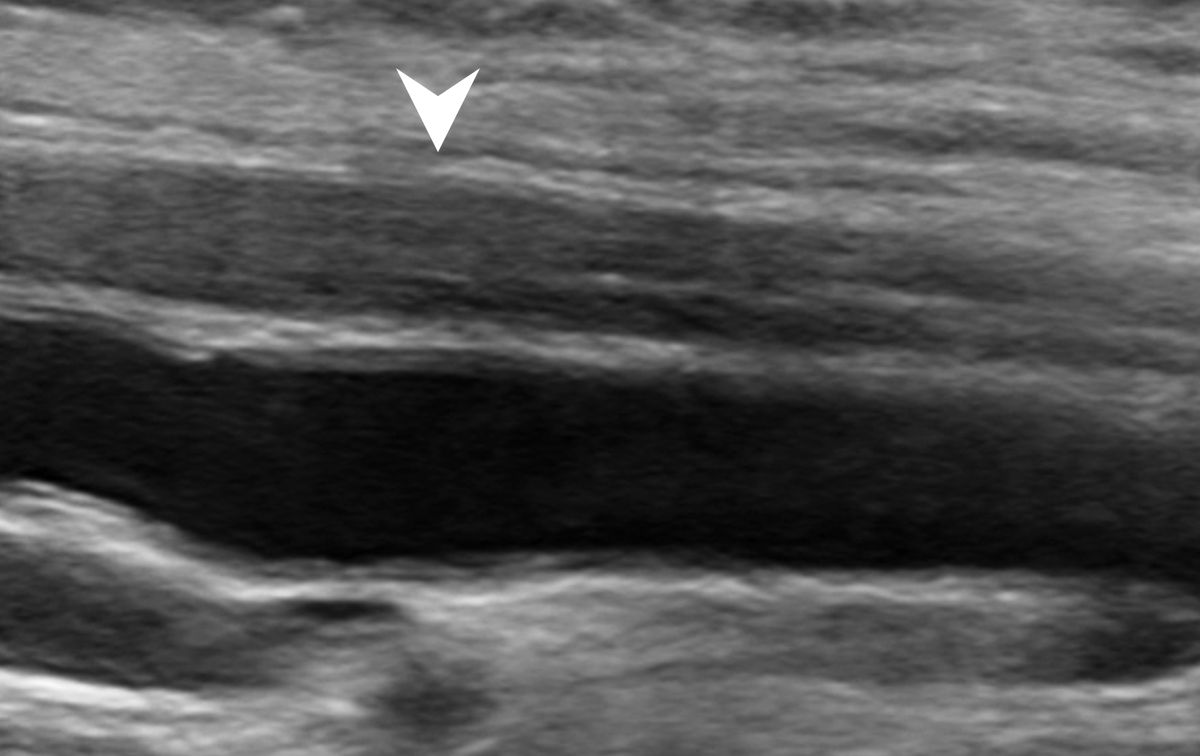

圖:超音波圖示下腫脹之神經。

陳小姐一開始先到神經內科就診,經過詳細的檢查,診斷為腕隧道症候群,乃因為正中神經在經過手腕處被上方韌帶壓迫所導致。經轉介到復健科接受治療。復健科醫師透過超音波仔細檢查發現,陳小姐的正中神經在通過手腕橫韌帶處呈現神經腫脹損傷之情形。

當出現以上症狀建議病患尋求專業復健科醫師的協助。醫師可藉由理學檢查在特定神經分布區域找到因為神經擠壓而產生的壓痛點。也可以經由超音波檢查確認神經是否因為擠壓、拉扯而出現腫脹發炎的狀況。